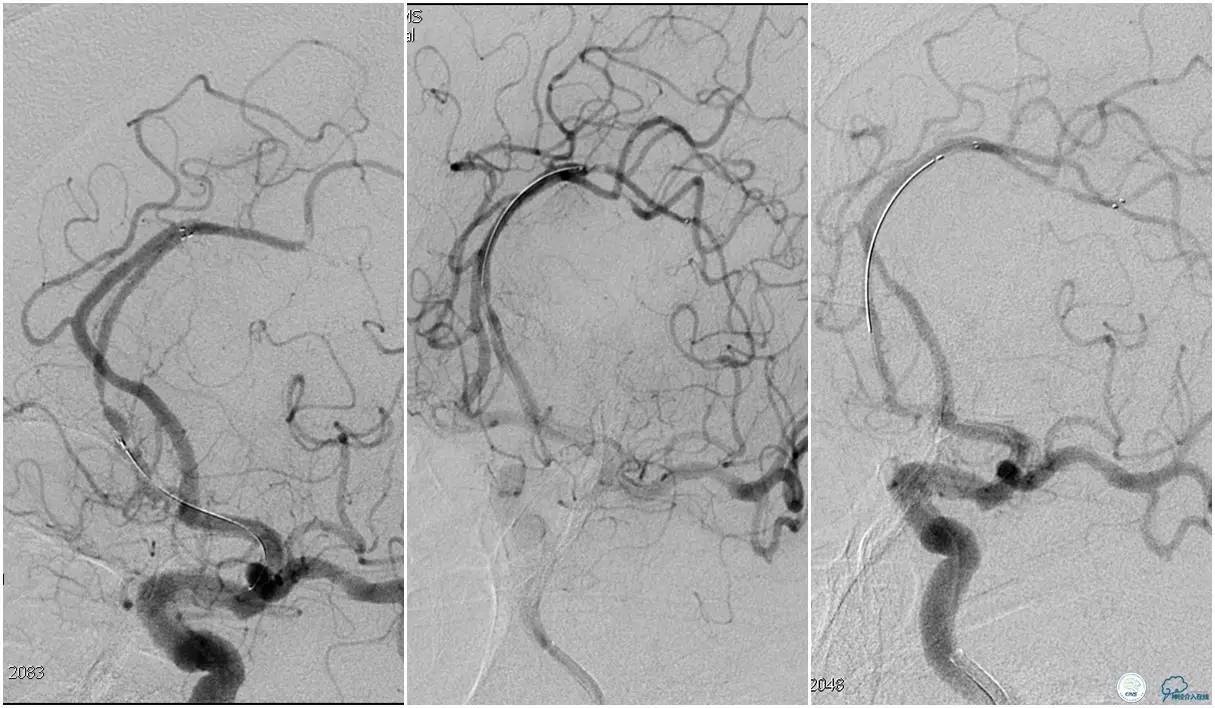

6F Envoy置于左侧颈内动脉C3段,选用Solitaire-FR 4*20mm支架释放于右侧大脑前动脉取栓1次,血流达TICI 2b。

Solitaire-FR 4*20mm支架释放于左侧大脑前动脉取栓1次,取出少许血栓重复造影左侧大脑前动脉胼周动脉开口后,右侧大脑前动脉A2段以远未显影,考虑栓子逃逸。

选用Solitaire-FR 4*20mm支架分别于右侧大脑前动脉A2-A3段,左侧胼周动脉,右侧胼周动脉取栓3次。

双侧大脑前动脉完全显影,TICI 3级,TOR 261min。